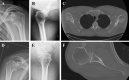

Introduction: Although age is considered to be the major risk factor of primary glenohumeral osteoarthritis (GOA), younger population may suffer from degenerative changes of the shoulder joint without evidence of any leading cause. The purpose of this study was to investigate the risk profile in young patients suffering from presumably primary GOA.

Methods: A consecutive group of 47 patients undergoing primary shoulder arthroplasty for early-onset GOA below the age of 60 years at time of surgery was retrospectively identified and prospectively evaluated. Patients with identifiable cause for GOA (secondary GOA) were excluded. The resulting 32 patients (mean age 52 ± 7 years; 17 male, 15 female) with primary GOA were matched by age (± 3 years) and gender to 32 healthy controls (mean age 53 ± 7 years; 17 male, 15 female). Demographic data and patient-related risk factors were assessed and compared among both groups to identify extrinsic risk factors for primary GOA. Patients were further subdivided into a group with concentric GOA (group A) and a group with eccentric GOA (group B) to perform a subgroup analysis.

Results: Patients had a significantly higher BMI (p = 0.017), were more likely to be smokers (p < 0.001) and to have systematic diseases such as hypertension (p = 0.007) and polyarthritis (p < 0.001) and a higher Shoulder Activity Level (SAL) (p < 0.001) when compared to healthy controls. Furthermore, group B had a significantly higher SAL not only compared to healthy controls but also to group A, including activities such as combat sport (p = 0.048) and weightlifting (p = 0.01).

Conclusions: Several patient-specific risk factors are associated with primary GOA in the young population, as well as highly shoulder demanding activities in the development of eccentric GOA. Consequently, a subset of young patients with eccentric primary GOA could in reality be secondary due to a muscular imbalance between internal and external rotators caused by improper weight training.